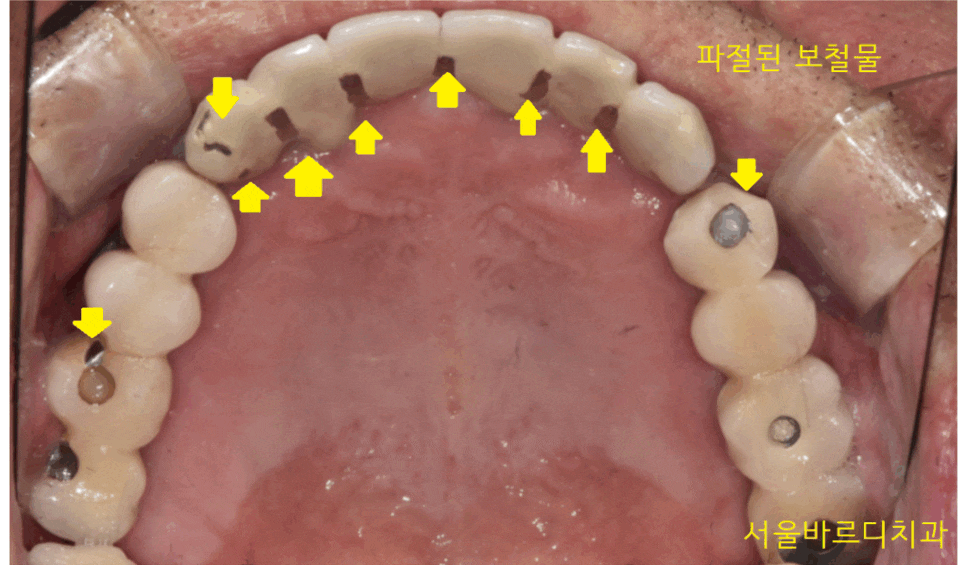

안쪽에서 봐볼까요~?

23.04.14

안쪽에서는 씹는 부위다 보니 더 많이 깨졌습니다.

보철물이 다 깨질 때까지

오래 쓰셨습니다.